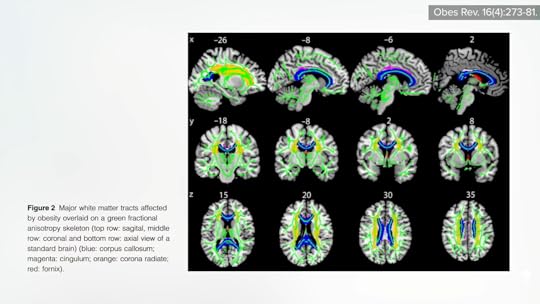

A review entitled “Does the Brain Shrink as the Waist Expands?” noted gray matter atrophy across all ages among those carrying excess body fat. It’s this reduced brain volume that has been correlated with lower executive function. As you can see below and at 1:42 in my video The Effects of Obesity on Dementia, Brain Function, and Fertility, compromised integrity of the rest of the brain—the white matter—suggests accelerated brain aging, even in young adults and children with obesity.